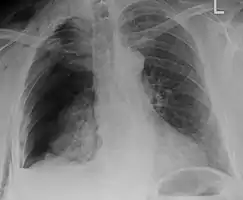

![]() | |

| An X ray showing multiple old fractured ribs of the person's left side as marked by the oval | |